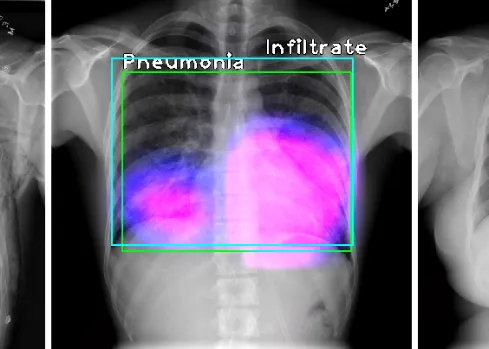

A recent ground-breaking project has made strides in lung cancer detection by developing advanced AI models for analysing chest X-rays. These sophisticated models are designed to detect lung nodules with high sensitivity and specificity, aiming to enhance diagnostic accuracy and reduce the likelihood of false positives and negatives. By leveraging cutting-edge deep learning techniques, the AI systems can identify potential malignancies that may be missed in manual reviews.

In addition to detecting nodules, the AI models provide detailed analyses of their size, shape, and density, offering radiologists valuable insights for more precise diagnosis and treatment planning. The project also seeks to improve decision-making regarding the need for further imaging, such as CT scans, thereby boosting overall diagnostic efficiency and accuracy.